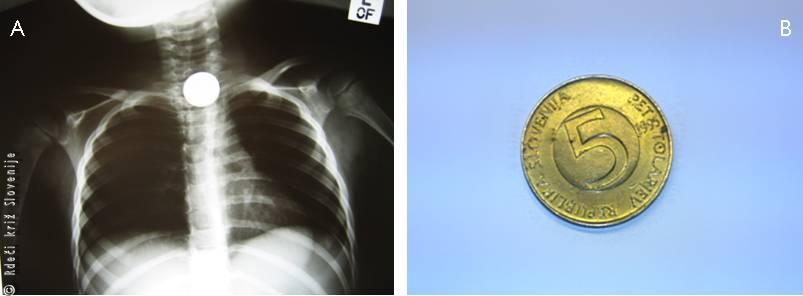

Starši 5-letne deklice ob prihodu na v zdravstveno ustanovo povedo, da se je deklica s prijatelji igrala pirate. Pri tem je v usta vzela 5-tolarski kovanec, da bi »preverila« njegovo pristnost. Kovanec ji je zdrsnil v grlo in tam obtičal. Pričela je kašljati in loviti sapo ter mahati z rokami. Ko sta v sobo prihitela starša, je bila modra v obraz, hip za tem pa se je stanje izboljšalo. Povedala je lahko kaj se je zgodilo, vendar je imela hripav glas. Tožila je za hudo bolečino v grlu, ki se je stopnjevala. Ker ni vedela, če je kovanec izkašljala, sta jo starša nemudoma odpeljala v bližnjo zdravstveno ustanovo.

Ob pregledu je bila deklica nekoliko vznemirjena, vendar je dihala normalno. RTG posnetek prsnega koša je pokazal kovinski tujek. Deklica je bila sprejeta na oddelek za otroško kirurgijo, kjer so odstranili kovanec, ki se je zagozdil v zgornjem delu požiralnika. Naslednji dan je bila odpuščena v domačo oskrbo.

Slika 9

A – RTG slika prsnega koša, kjer je viden kovinski tujek.

B – 5-tolarski kovanec.